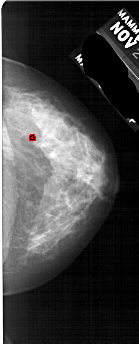

A_1736_1.RIGHT_MLO

RIGHT_MLO LINES 5341 PIXELS_PER_LINE 2611 BITS_PER_PIXEL 12 RESOLUTION 43.5 OVERLAY

FILE: A_1736_1.RIGHT_MLO.OVERLAY

TOTAL_ABNORMALITIES 1

ABNORMALITY 1

LESION_TYPE CALCIFICATION TYPE PLEOMORPHIC DISTRIBUTION CLUSTERED

ASSESSMENT 3

SUBTLETY 1

PATHOLOGY BENIGN

TOTAL_OUTLINES 1

BOUNDARY